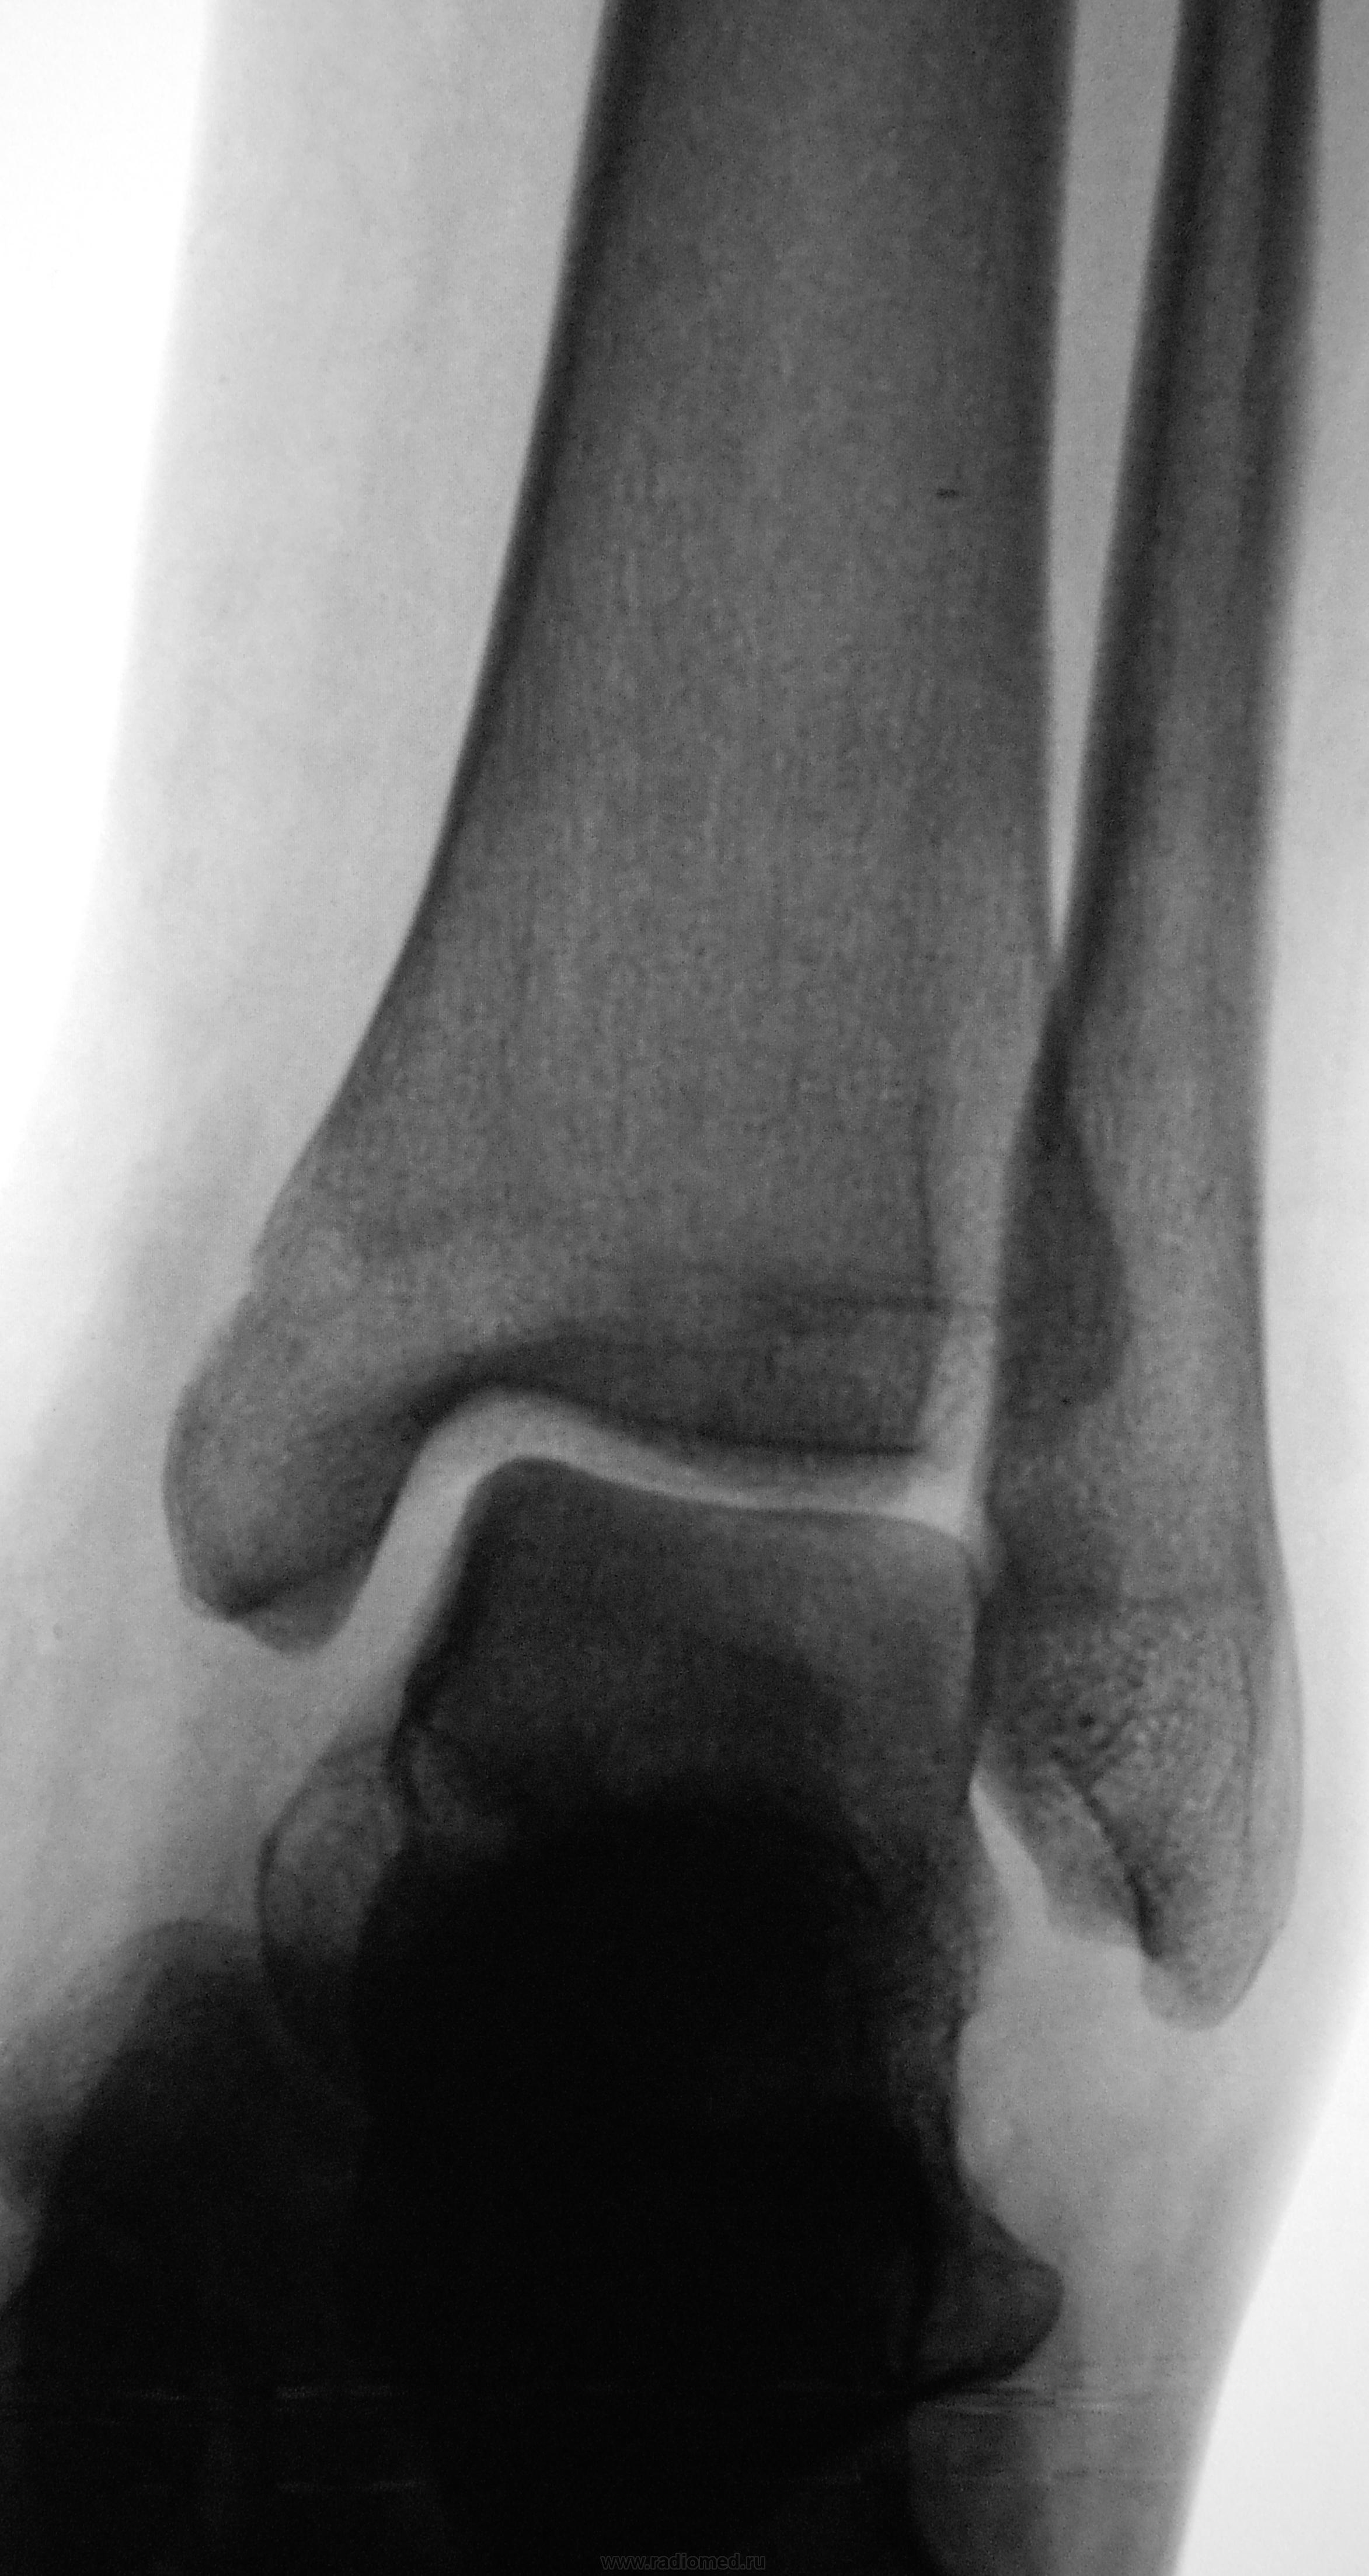

Разве есть где-то перелом?

Я в сомнении, вот и выставил..., вроде нет...

Думаю, что тоже "нет", небольшое краевые полоски типа дефектов за счет недавно закрывшихся зон роста. А болеть могут и разрывы связочного аппарата.

+1 за разрыв связок

Я уже приготовился написать норму, но глаз упорно цеплялся за контур.

Сказал лаборанту сделать косую проекцию

Только после последнего снимка и на стандартных проекциях, очень внимательно приглядевшись, увидел линию перелома...

Линия перелома

Снимаю шляпу! Я думала, что этот контур закрывшаяся зона роста.